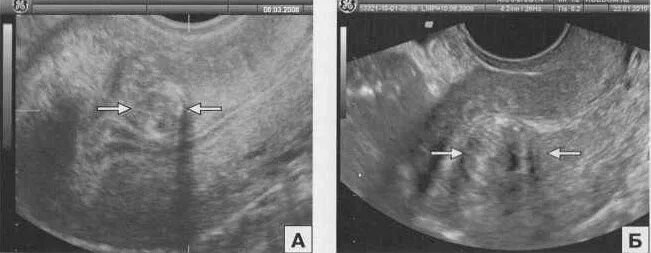

Эндометрий 9 мм